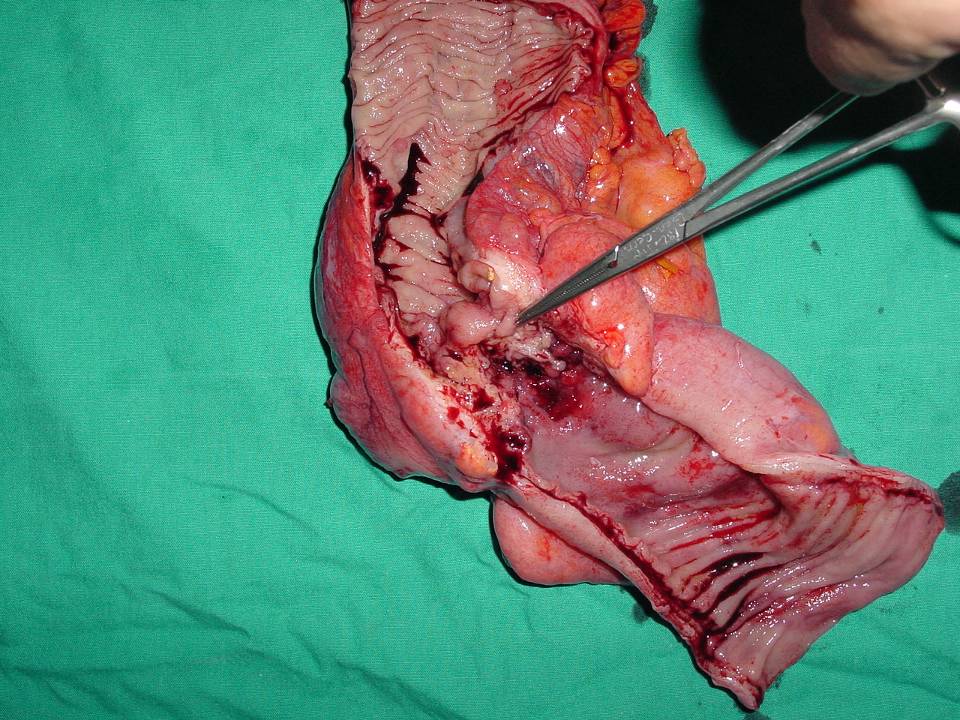

İleri Radyolojik Yöntemler

• Bilgisayarlı tomografi (BT)

• Manyetik rezonans görüntüleme (MR)

• Özellikle kitle oluşturan lezyonlarda.

• İlk aşamada kullanılmaları önerilmez.

• Konulmuş olan bir tanı sonrası yaklaşımı planlamada yardımcı olurlar.